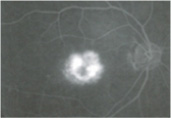

眼底検査

加齢黄斑変性